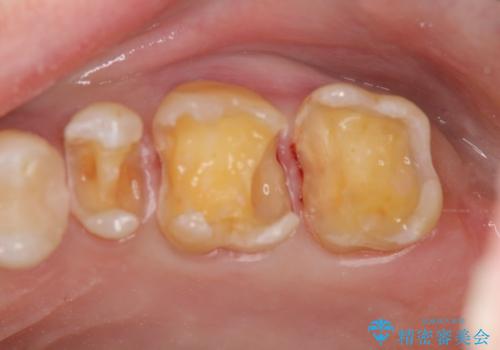

銀歯を丁寧に除去すると、銀歯の下で虫歯の再発やセメントの劣化が確認されたので、拡大鏡・マイクロスコープを用いて虫歯のみを丁寧に取り除いたのち、精密なセラミッククラウンの製作を進めます。

拡大鏡・マイクロスコープを用いて虫歯を丁寧に除去することで、健全な歯質や神経を守ることにつながります。